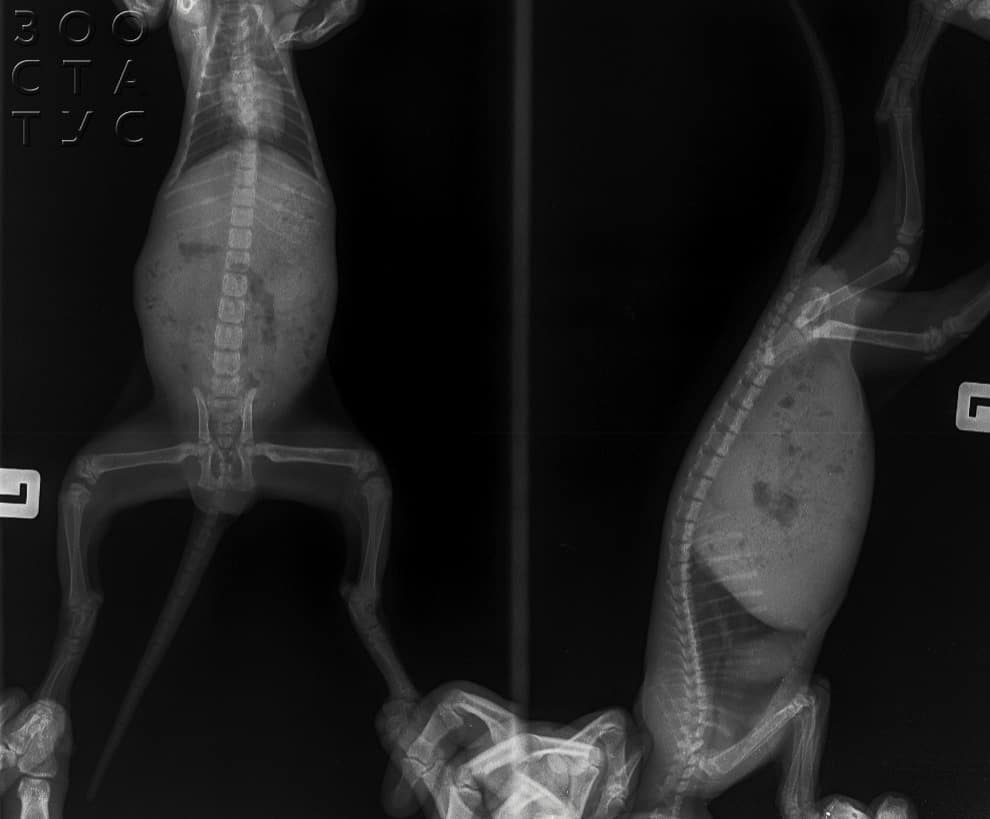

Вторичный (или алиментарный, то есть обусловленный питанием) гиперпаратиреоз — это патология, вызванная дефицитом в рационе котят и щенков кальция и неправильным соотношением кальция к фосфору (когда фосфора значительно больше, чем кальция — это неправильно). При избытке фосфора и дефиците кальция в дело вступает паратгормон. Если про витамин D мы говорили, что это проводник между кальцием и костью, то паратгормон — это, условно говоря, управляющий этим проводником :) Когда фосфора становится больше, чем кальция, организм паникует, эту проблему надо решать — и вырабатывается больше паратгормона, что приводит к тому, что кальций из костей обратно вымывается в кровь. Потому что поддержание постоянного состава крови для организма важнее, кальций нужен не только в костях, и его срочно достают из депо — из костной ткани. В результате снижается плотность костей — такие кости на рентгене выглядят практически прозрачными, сливаясь с мягкими тканями. Это, во-первых, больно, потому что надкостница очень богата нервными окончаниями, а во-вторых, это приводит к патологическим переломам. В результате этих двух факторов котенок или щенок на ранних стадиях снижает активность, прекращает бегать и прыгать, проявляется та самая «неправильная» походка, на более поздних опороспособность вообще исчезает.

Проявления. Рахит приводит к нарушению зон роста, искривлению костей. Вторичный гиперпаратиреоз приводит к снижению плотности костей, и опосредованно к переломам. Искривлённые кости и «прозрачные» (низкой плотности) кости — это разное.